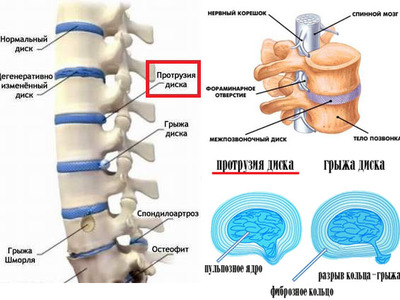

Мрт картина дегенеративно дистрофических изменений пояснично крестцового отдела позвоночника